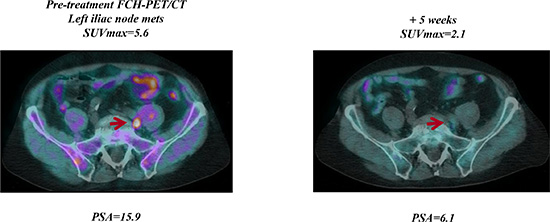

FCH-PET/CT scanning showed 3 CR, 11 PR, 6 SD, and 22 PD, but in 6 of 12 pts with initial PD at FCH-PET/CT a bone flare phenomenon was suspected due to a stable disease at 3-month CT scan associated with a progressive decline of PSA. In one case suspected for bone flare, the PET scan was not repeated due to severe intestinal infection with treatment interruption and following clinical deterioration. In another patient who had a 3-month PSA decline of 60% with SD at 3-month CT scan, the follow-up FCH-PET/CT scanning after 11 weeks confirmed PD with rapidly increasing PSA levels. Thus, overall, bone scan flare, as defined by the combination of PSA decline, initial flare, and subsequent improvement or stability in the following FCH-PET/CT scanning was observed in 4 of 42 (10%) evaluable patients and 4 of 24 (17%) responsive cases. The clinical characteristics of these 4 cases were not significantly different from the study population as a whole, median age was 71 years (range, 57 to 78), median PSA level at baseline was 15.5 ng/mL (range, 1.5–92.2), the maximal decline of PSA was 91%, 73%, 64% and 37%, respectively. The latter case who had a very low baseline PSA level of 1.5 ng/mL and PSA decline to 0.9 ng/mL (37%, lower than the threshold of 50%) was also considered to be of interest and is reported as bone flare. A PSA flare, defined as an initial PSA increment followed by a decline below the PSA baseline level, was reported in one case of bone flare, but also in another patient without bone flare. Of 4 patients with FCH-PET/CT bone flare, 3 had PD after 9, 11 and 13 months, respectively, while one is continuously progression free after 22+ months. A CR was achieved at follow-up FCH-PET/CT in 3 of the 26 (12%) evaluable patients, and was associated with undetectable PSA levels (< 0.03 ng/mL) in 1 case after 5 months on abiraterone. Of 3 patients with nodal disease only, one obtained a CR at first FCH-PET/CT and 2 a PR with a mean SUVmax reduction of 55% and 70%, respectively. Figure 1 to 3 show examples of early FCH-PET/CT effects of abiraterone, including an example of bone flare.

Figure 1: Early FCH-PET/CT complete response on abiraterone treatment. Baseline FCH-PET/CT shows a single left iliac nodal lesion, 5 week FCH-PET/CT resolution correlated with PSA decline and then with undetectable PSA levels (PSA < 0.03 ng/mL) after 6 months of abiraterone therapy.